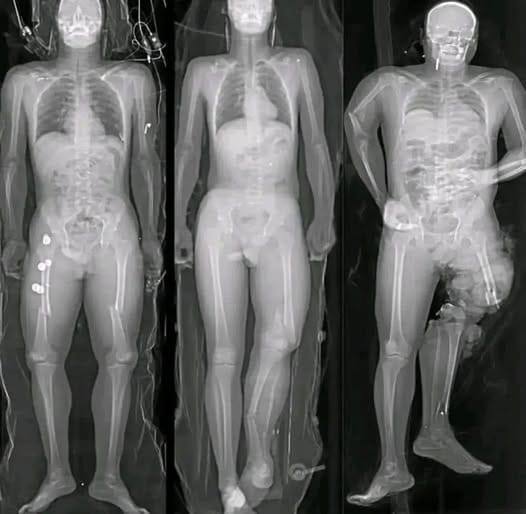

In recent months, a wave of alarming images and short messages has circulated widely across social media platforms, often accompanied by phrases such as “If you got the COVID vaccine, you should know this.” Many of these posts feature dramatic visuals—most notably illustrations of syringes aimed directly at the human heart—designed to provoke fear and urgency. While the images are striking, they rarely provide verified medical context. Instead, they rely on emotional reaction rather than evidence.